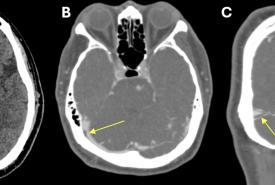

FIGURE 1: (A) A left periurethral mass extending from the left periurethral space to suburethral region measuring 3 cm x 5 cm; (B) Midsagittal view of the pelvic floor showing a cystic mass (*) dorsal to the urethra (U) measuring 2.17 cm x 2.78 cm on translabial perineal ultrasound (TPUS); (C) TPUS view demonstrating a periurethral mass dorsal to the urethra measuring 4.22 cm (width) x 1.99 cm (vertical dimension). (SP: Symphysis pubis; Ut: Uterus; CX: Cervix)